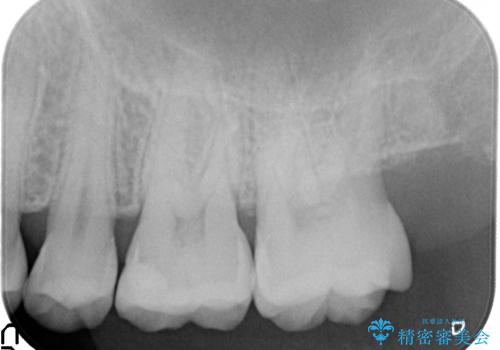

治療前の写真では虫歯はわかりにくいですが、レントゲンではっきり見えます。

虫歯は外の入り口は小さいままで、中で広がっていることが多いため、要注意です。

口の中を目で見てわかるレベルの虫歯ですと、進行してしまっています。

虫歯はレントゲンを取らないと、発見できません。

歯科検診はあくまで余程の状態のスクリーニングですので、きちんとレントゲンを定期的にとって、早期に治療することが重要です。